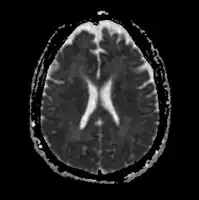

The diagnosis of hepatic encephalopathy is a clinical one, once other causes for confusion or coma have been excluded; no test fully diagnoses or excludes it. Serum ammonia levels are elevated in 90% of people, but not all hyperammonaemia (high ammonia levels in the blood) is associated with encephalopathy.[3][8] A CT scan of the brain usually shows no abnormality except in stage IV encephalopathy, when brain swelling (cerebral oedema) may be visible.[8] Other neuroimaging modalities, such as magnetic resonance imaging (MRI), are not currently regarded as useful, although they may show abnormalities.[14] Electroencephalography shows no clear abnormalities in stage 0, even if minimal HE is present; in stages I, II and III there are triphasic waves over the frontal lobes that oscillate at 5 Hz, and in stage IV there is slow delta wave activity.[3] However, the changes in EEG are not typical enough to be useful in distinguishing hepatic encephalopathy from other conditions.[14]